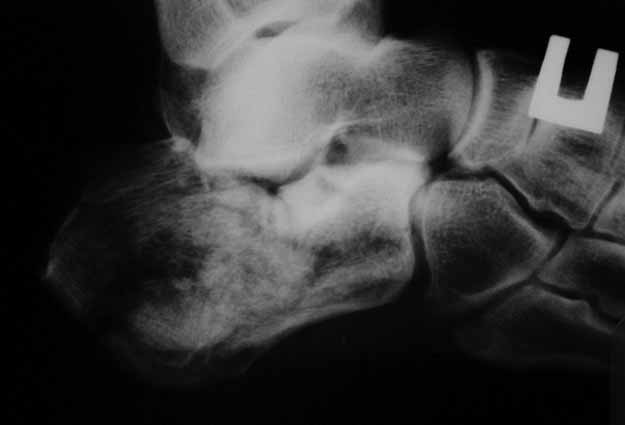

КТ перелома пяточной кости Пациент 60 лет с производственной травмой-закрытые переломы правой пяточной кости, тибиального плато слева поступил в феврале с.г. На 4 сутки выполнена открытая репозиция, остеосинтез внутрисуставного перелома голени, ручная репозиция пяточной кости. Через три месяца начал ходить с нагрузкой на обе ноги. Консолидация голени с полным восстановлением функции колена. Правая стопа умеренно отечна, продольно распластана, длительная ходьба вызывает боли и увеличение отека. Прошел несколько курсов ударно-волновой терапии, грязелечение, боли и отек уменьшились. В наших планах -оформление на ВТЭК, через год возможно выполнение подтаранного артродеза.Но после производства КТ в августе появились сомнения в консолидации перелома.Ранее у нас не было опыта КТ переломов стопы и сканы привели в замешательство.Прилагаю снимки со дня поступления, августовские пациентом не представлены.С благодарностью примем советы коллег.

Данное исследование сделано в неправильной позиции стопы, стопа находится под прямым углом. Но несмотря на это, здесь можно увидеть, что латеральная стенка смещена, фиброз между фрагментами и варусное смещение пятки.

Топография зависит от позиции пятки в пространстве и неправильное положение закрывает обзор нужных структур. Важными структурами в исследовании пятки является задняя фасетка, бугор и боковые стенки. Существует специальные рентгенснимки, показывающие импинджмент с лодыжкой, а также положение бугра. Для КТ стопу надо инклинировать под 30 градусов, иначе можно пропустить важные переломы.